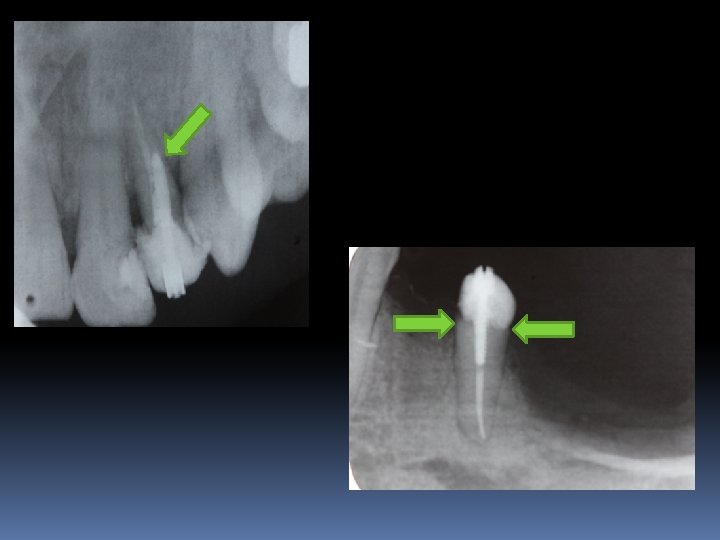

Post core yapım teknikleri: Kesim tamamlanınca ‘Peezo’ adı verilen mikromotor ucu, restorasyonu yapılacak dişin periapikal filmi üzerine tutularak, elde edilmek istenilen kanal boyutu işaretlenir.

Post core yapım teknikleri: Daha sonra işaretli noktaya ulaşıncaya kadar yavaş tur kullanılarak peezo ile istenilen boşluk elde edilir. Bu boşluk istenilen çapa çıkarılana kadar sırasıyla kalınlaşan gates glidden ya da peezo frezler kullanılır. DİKKAT SAKIN AEROTOR KULLANMAYIN.